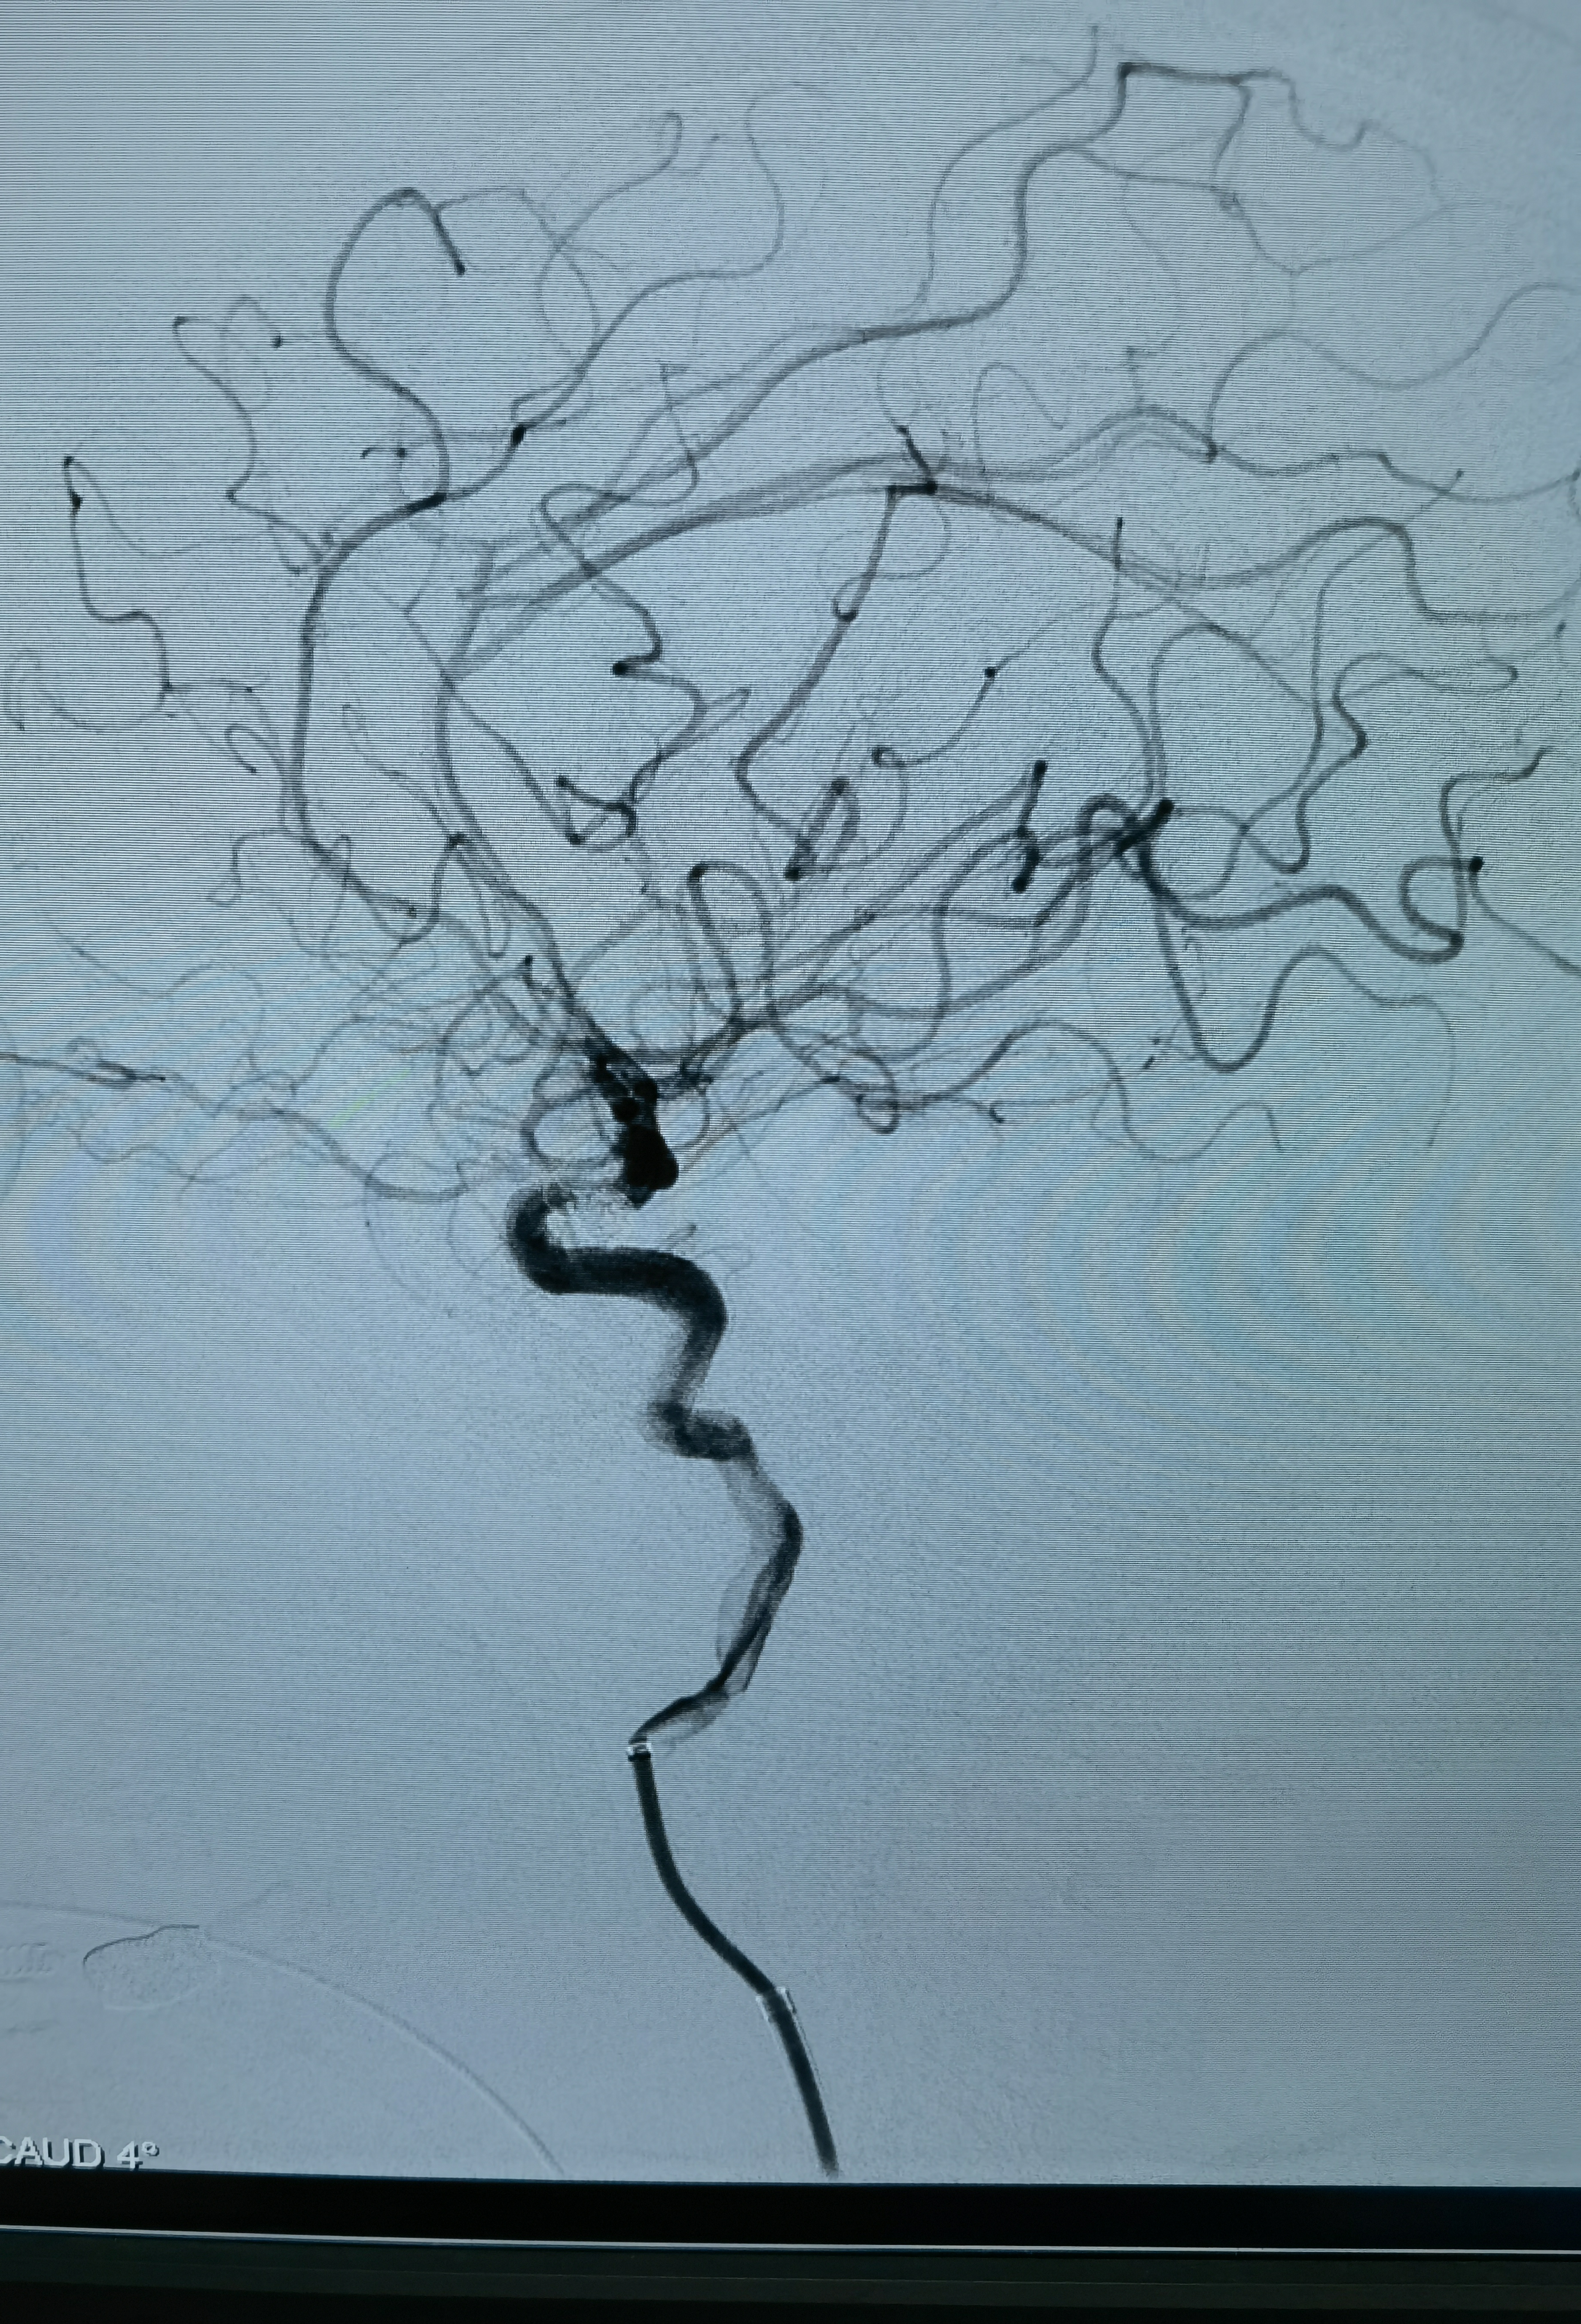

术后正位造影

术后侧位造影

术后顺便造了左侧颈内动脉